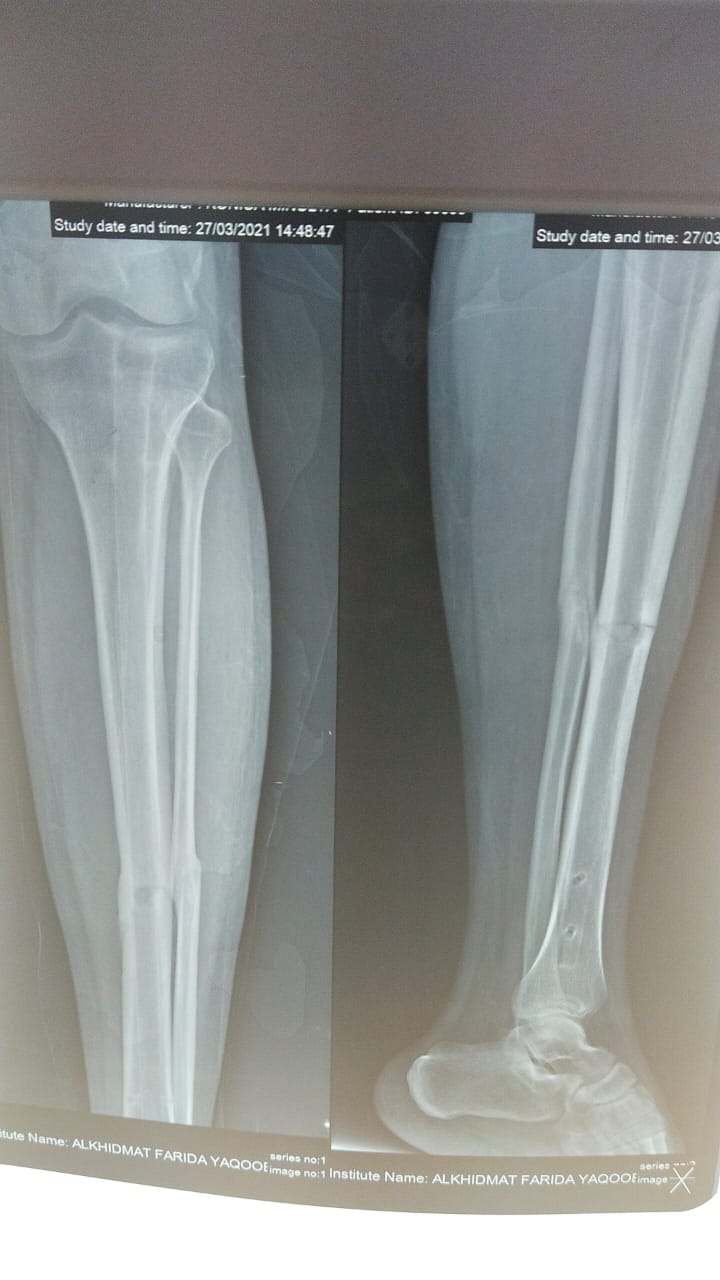

Dear Sir/Madam, my younger brother had accident on bike in Oct-2019 & his leg bone break then doctor advise to attach rod but due to feeling pain because of rod is 2 inch long in size & during walk he feels pain, so my brother consult with doctor to remove this rod then doctor agreed to remove this rod, & last month 18-Feb-2020 doctor removed his rod & bone is already jointed but on 27-march-2020 he is walking at home and suddenly he feels current in his leg at rod attaching area & cant walk anymore then we took him to the hospital & done x-ray (X-ray attached) & after x-ray doctor told that his bone already break at same area, & doctor told to again attach same rod in same area for forever, Kindly please advise us what to do, & where we will decide to done his operation again.

His rod is removed too early and now he has developed hypertrophic nonunion. Best is to get surgery again with reamed nail in dynamic mode.

Consult any good experienced Orthopeadic surgeon in your area: My plans about this patient would be : First to rule out infection ( by inspection and some blood tests ) secondly if there is no infection will go for exchange IM Rod a technical strategy and the best option to bring healing of this fracture and if there is infection then I would go for Antibiotic Rod first . I. This case Rod was malplaced and malpositioned .